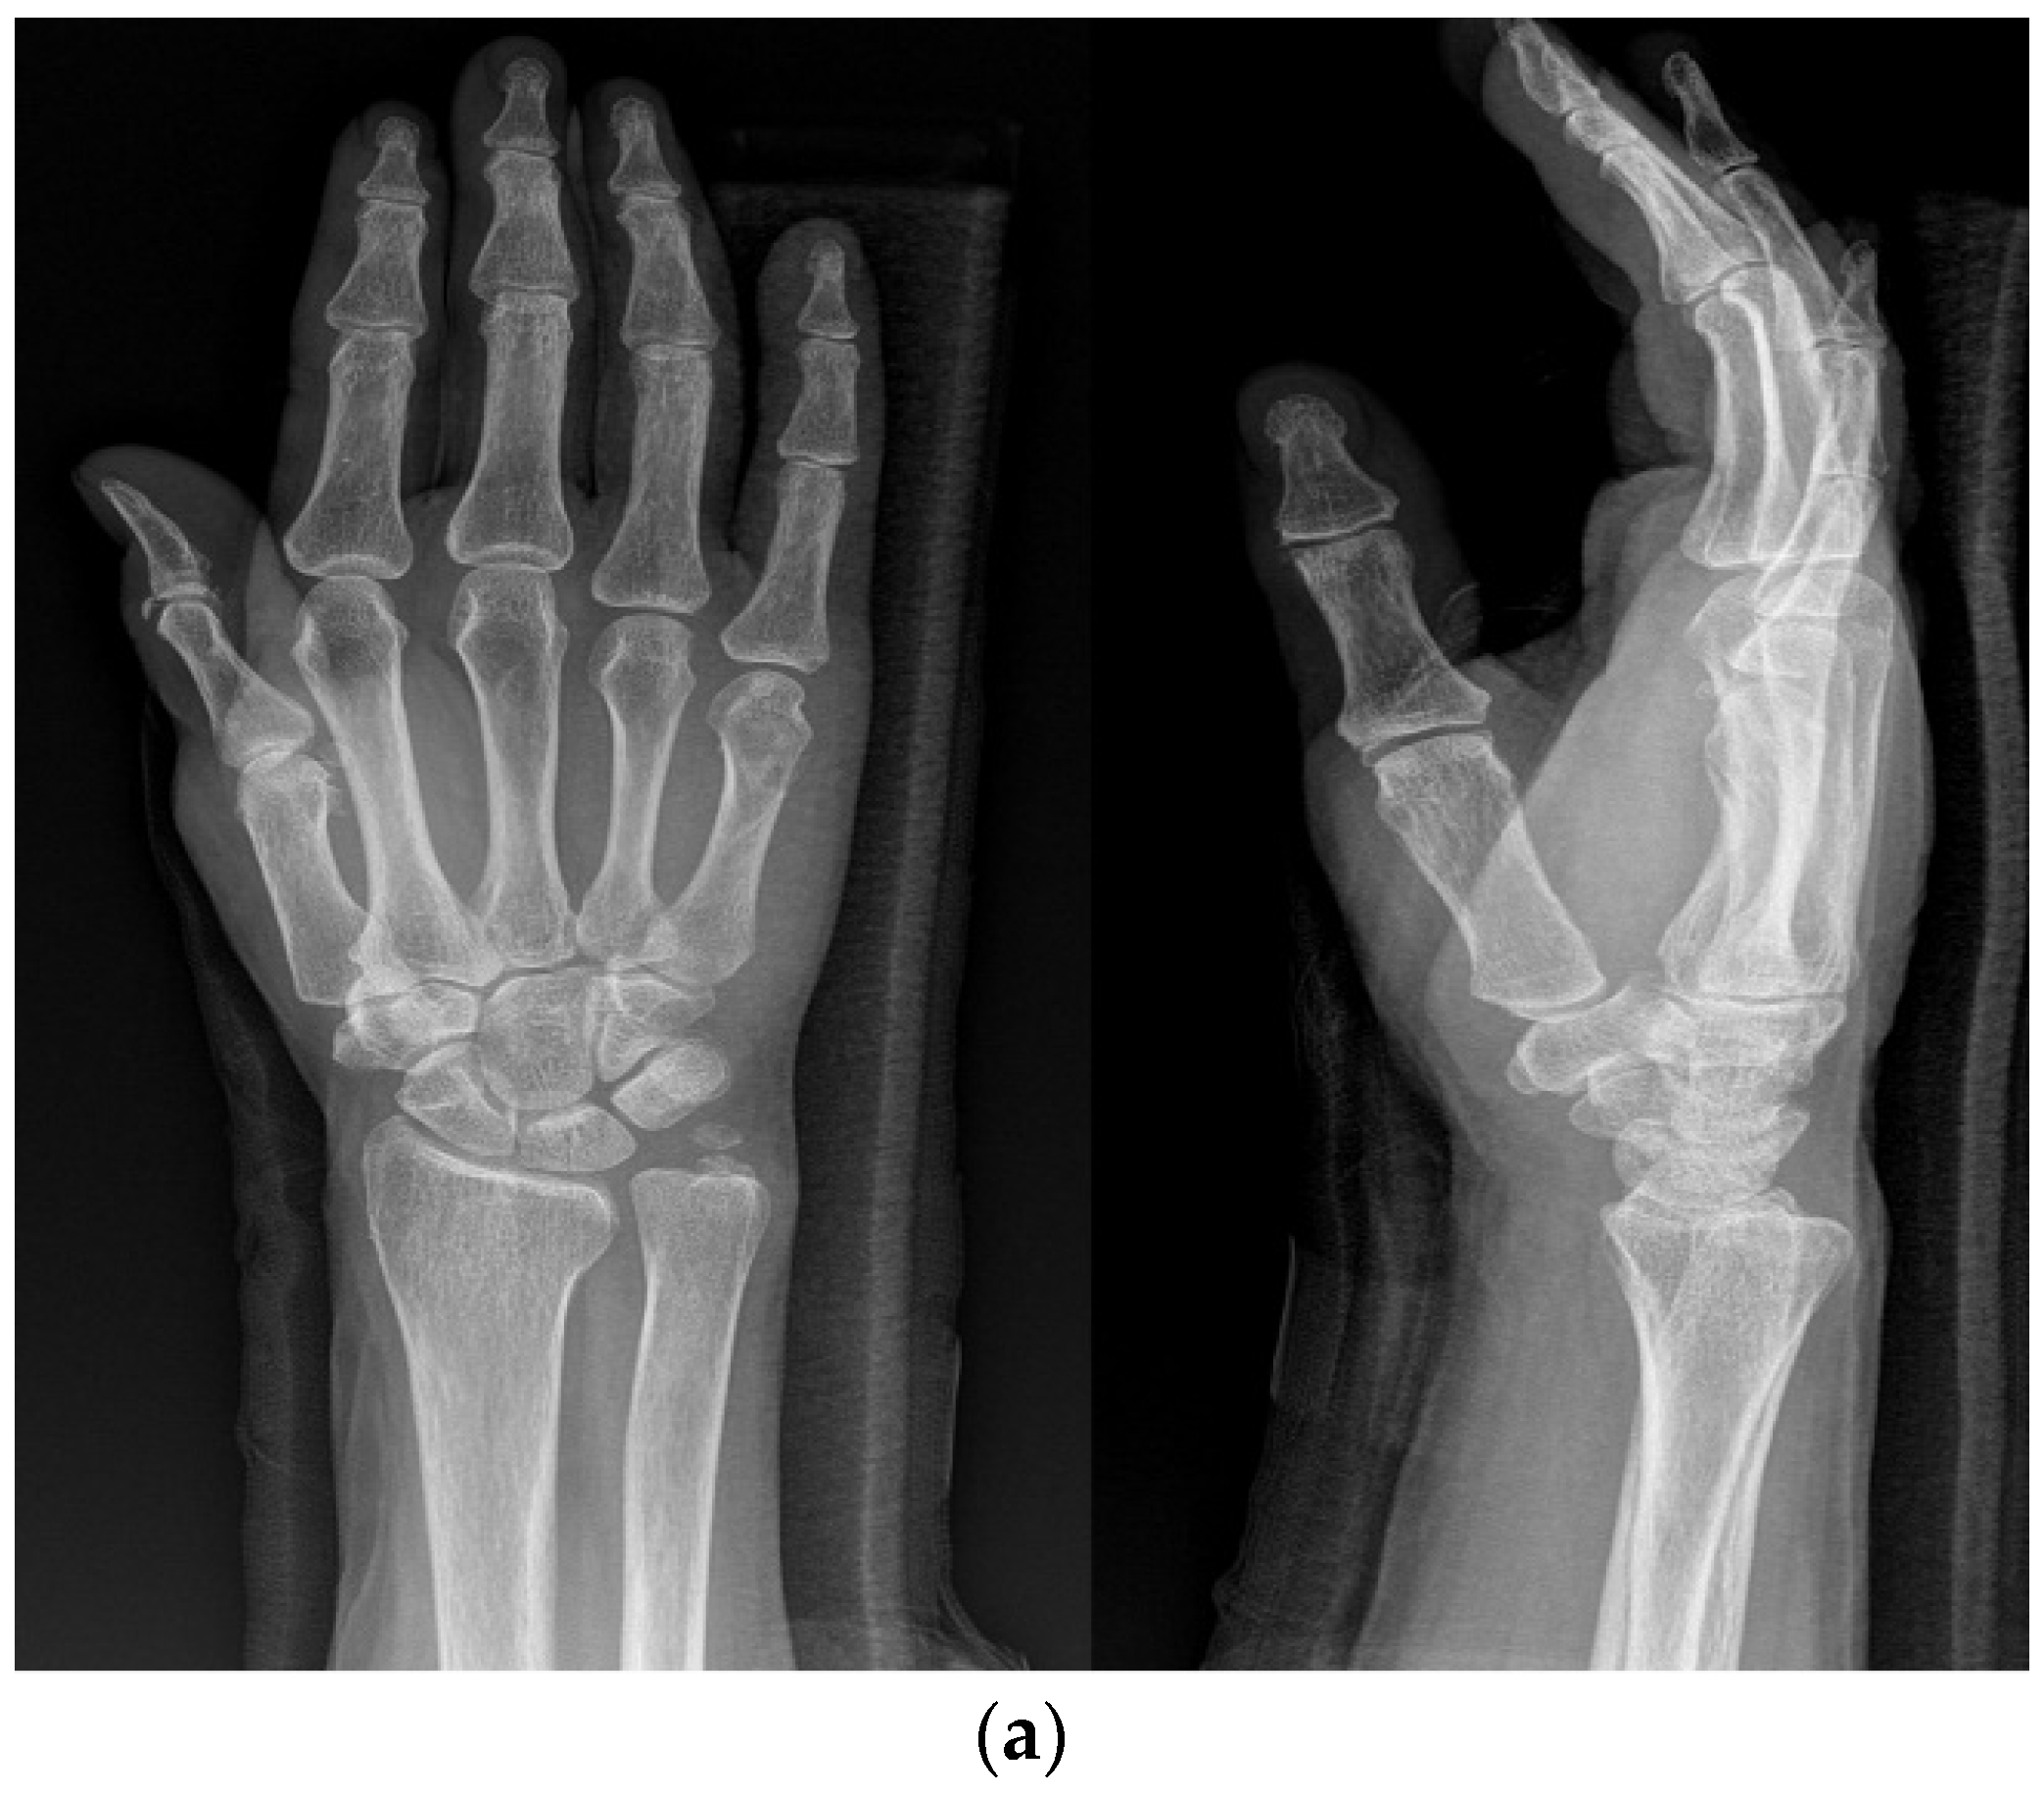

2.2. Methods

2.3. Surgical Technique